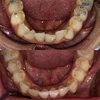

Diş Çapraşıklığı

Diş ve Diş eti hastalıkları